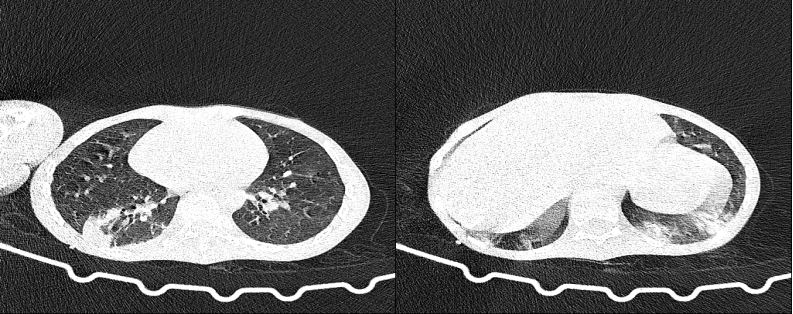

近日,我院儿童病院PICU病区收治了一位的特殊的患儿,因”颅内感染、意识障碍”从外院转入,来我院后诊断为死亡率极高的“急性坏死性脑病”,在近3个月病期内,经历了昏迷、惊厥持续状态、肝衰竭、横纹肌溶解及肾衰竭,以及多重感染,患儿遭遇了一次次生命危机,在全体儿科人的努力下又一次次成功化解。半个月前,患儿终于迎来了意识清醒,能和医护、家人交流了。但好景不长,患儿再次出现体温上升,同时血氧饱和度下降,最低只有60%。胸部CT检查发现双下肺可见大片高密度影,影像和痰培养均提示白色念珠菌感染,虽经积极抗真菌治疗,但患儿体温下降不明显,复查胸部CT病变范围较前扩大,因此行支气管镜检查和灌洗对于患儿的进一步治疗迫在眉睫。可是患儿病情本身很复杂,全身状态极差,是否能耐受支气管镜检查及灌洗,灌洗是否会导致感染扩散,都是亟待解决的问题。

第二天,在儿童病院PICU病区,由王慧渊主治医师操作,韦飞主管护士配合对患儿进行了床旁支气管镜检查,镜下可见右肺下叶支气管开口处痰栓壅塞,立即予以负压吸引将清除痰栓,并对肺泡灌洗行病原学检测,结果提示除真菌感染外,还有细菌混合感染。经过支气管镜灌洗术以及时的调整治疗方案,术后第二天患儿体温未再反复,血氧饱和度维持在95%以上,后期复查感染指标也明显好转。在大家的努力下,危机再次解除。